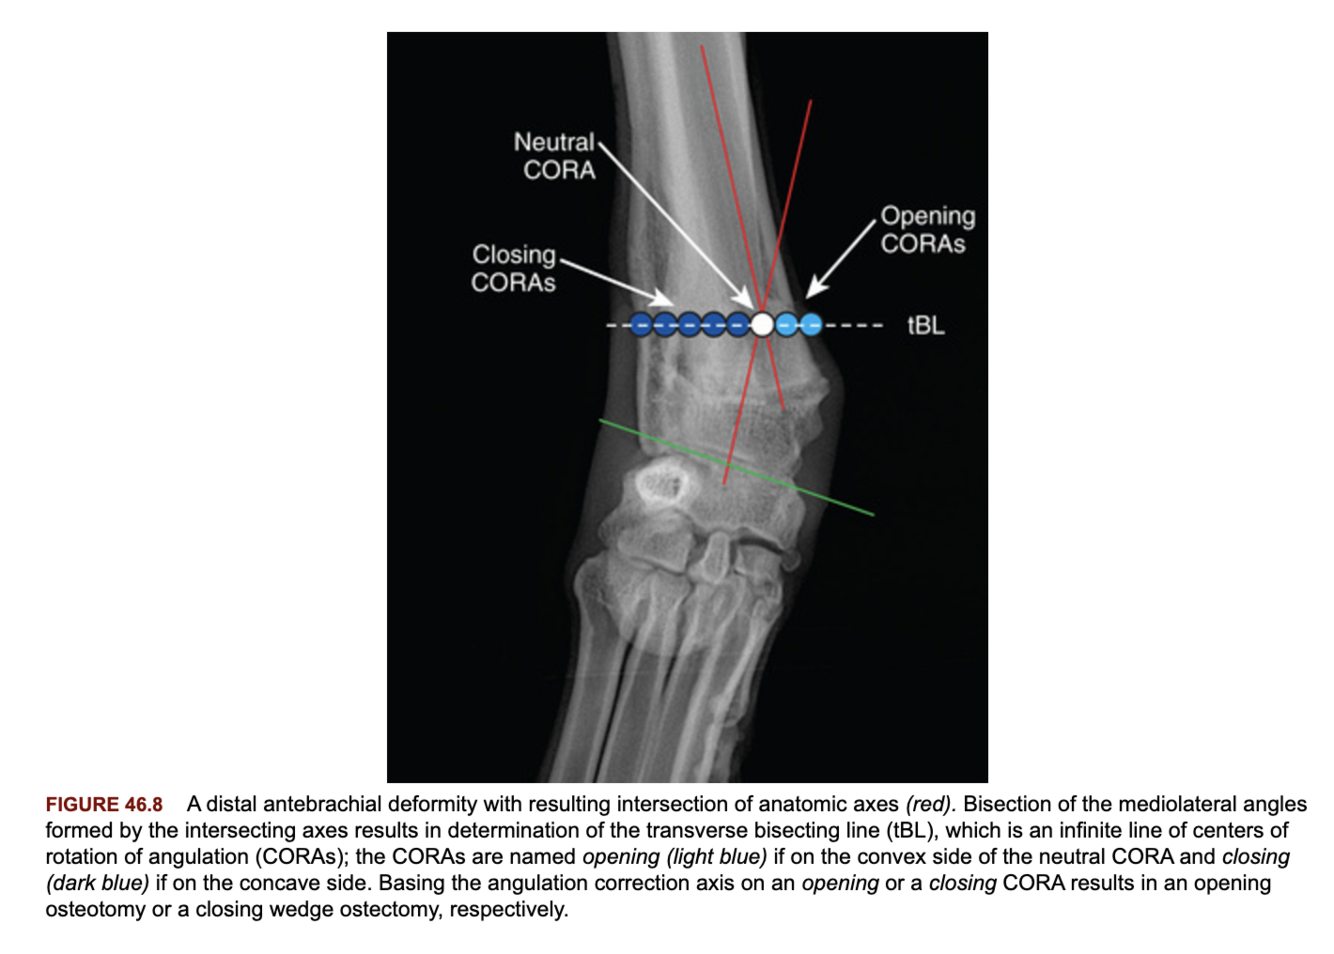

What is a CORA?

The center of rotation of angulation and is essentially the apex of an angular limb deformity.

Has a location, plane and magnitude.

How is a CORA measured?

The intersection of the axes of the bone as drawn through the joint orientation lines. The angle of the axes is based off the contralateral limb or library of reference values.

What is an opening and closing CORA?

Closing CORA: points along the transverse bisecting line on the concave side.

Opening CORA: points along the transverse bisecting line on the convex side.

They determine whether a closing or opening wedge will result in correction of the deformity when the angulation correction axis (ACA) is based on their side.